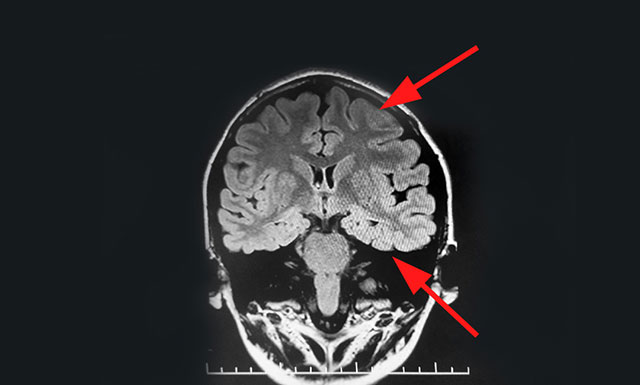

經檢查,腦電監(jiān)測崔麗華主任根據腦電圖監(jiān)測分析指出,患者雙側有癲癇波,左側較為嚴重。磁共振檢查,患者顳葉、額葉、海馬結構異常。既往史顯示,患者4個月時有肺炎高熱病史,并伴有抽搐等癥狀。

▲ 通過系列檢查最終明確患者致癲灶

患者經系統內科藥物治療不佳,確診為藥物難治性癲癇,經過系列檢查最終明確患者致癲灶位于左側海馬、左側顳葉、左側額葉。手術指征明確,未見明顯手術禁忌癥。